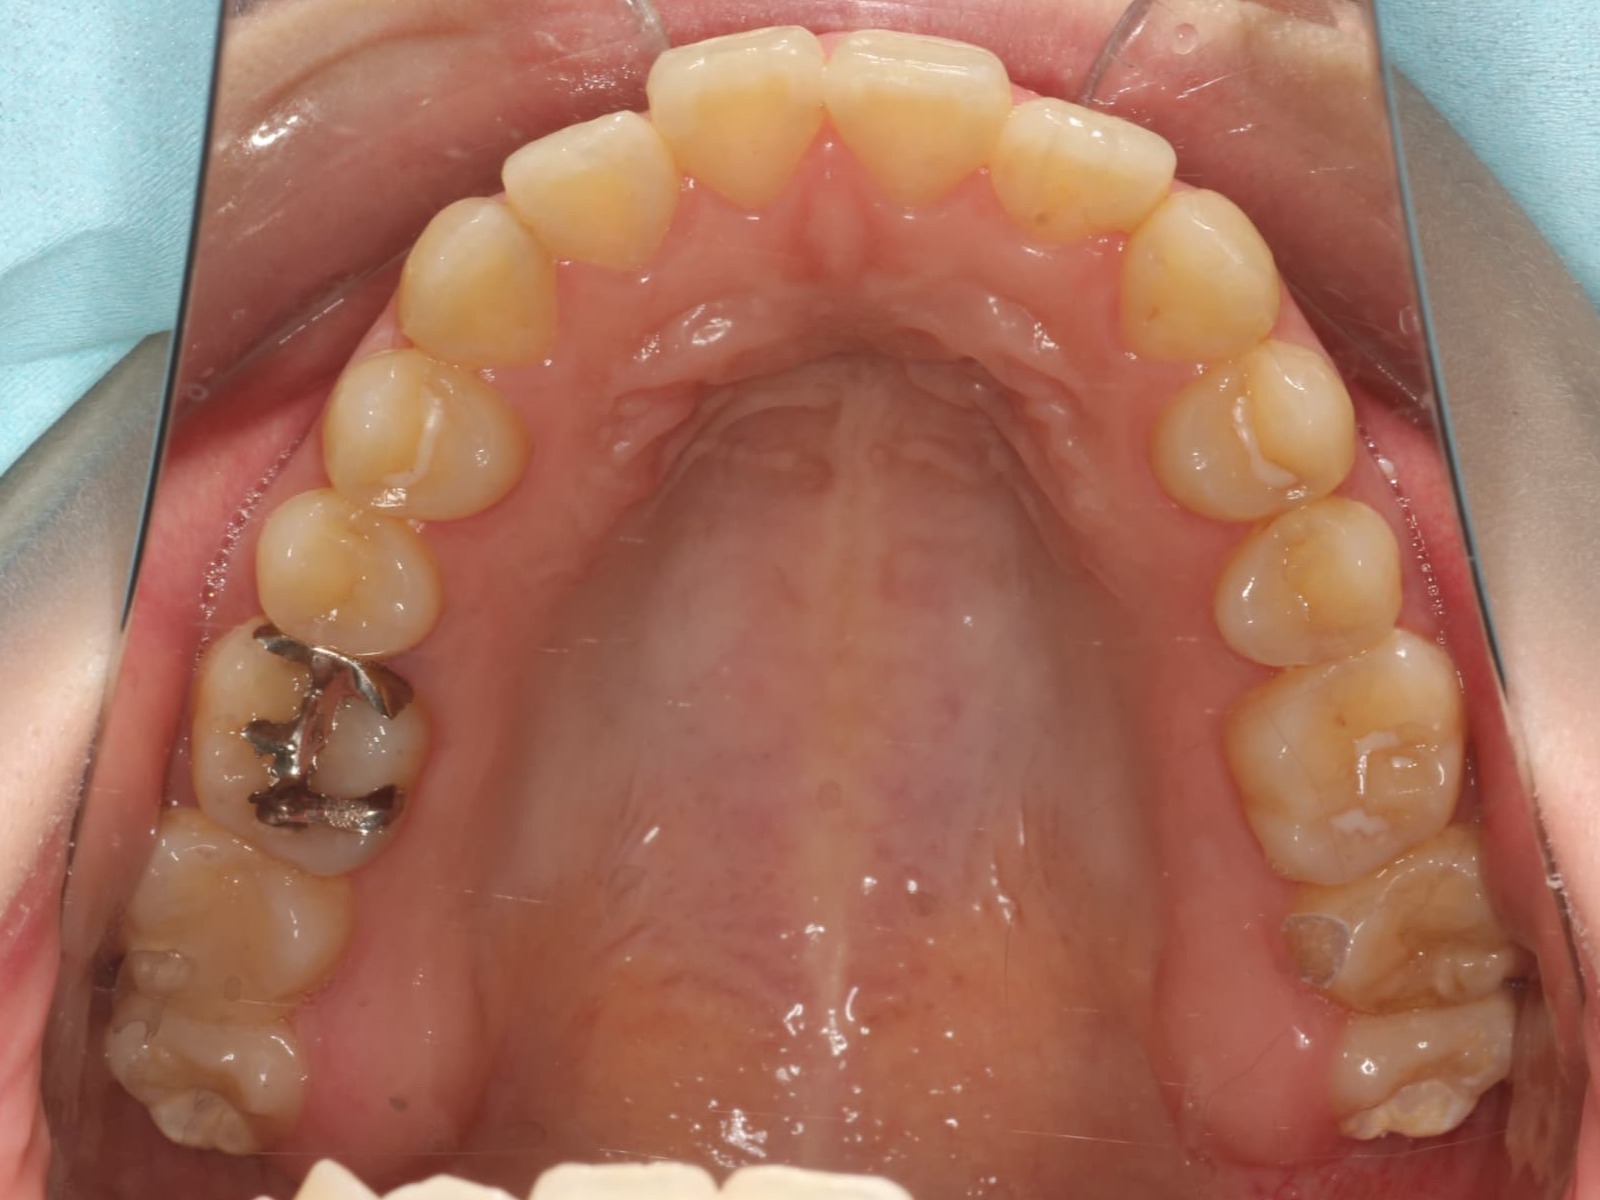

事例紹介

Before After

上顎前突(口ゴボ)

症例概要 / Case details

- 治療名: インビザライン(抜歯矯正)

- 主訴: 出っ歯を治したい

- 期間・回数: 7ヶ月 / 来院3回

- 費用の目安(自費・税込換算の目安): 770,000円(税込)

- リスクについて:使用時間に応じて歯の移動の結果が変わる場合があります。

治療内容の要点

口元を下げるために、前から4番目の歯(第一小臼歯)を抜歯し、そのスペースを利用して前歯を後ろに下げました。

歯は骨に埋まっているため、CT撮影をすることで骨の厚みを把握し、その中で歯が安全に収まるように治療計画を組みながら確実に移動させていきました。

無事前歯が後方に移動し、Eラインが綺麗に整っています。